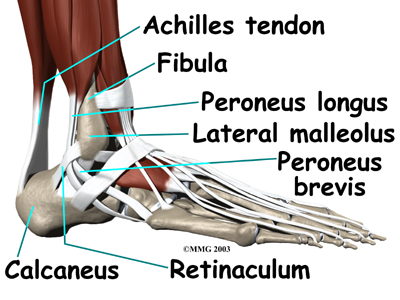

The primary muscles supporting the are the peroneals. These two muscles and their tendons lie along the outside of the lower leg bone (fibula) and cross behind the lateral malleolus (the outside ankle bone).

The tendons of the peroneal muscles pass together through a groove behind the lateral malleolus. The tendons are kept within the groove by a sheath that forms a tunnel around the tendons. The surface of this sheath is reinforced by a band of ligament called a retinaculum. Contracting the peroneals makes the tendons glide in the groove like a pulley. This pulley action points the foot downward (plantarflexion) and outward (eversion).

The main cause of peroneal tendon subluxation is an ankle sprain. A sprain that injures the ligaments on the outer edge of the ankle can also damage the peroneal tendons. During the typical inversion ankle sprain, the foot rolls in. The forceful stretch on the peroneals can rip the retinaculum that keeps the peroneal tendons positioned in the groove. As a result, the tendons can jump out of the groove. The tendons usually relocate by snapping back into place.

Differences in the anatomy of the groove may predispose some people to peroneal tendon subluxations. The groove may be too shallow. Or the ridge that helps deepen this groove may be too small or even absent. Sometimes, the retinaculum that keeps the tendons in the groove may be too loose. In these cases, patients may not recall any injury to explain the persistent snapping of the peroneal tendons.

Patients describe a popping or snapping sensation on the outer edge of the ankle. The tendons may even be seen to slip out of place along the lower tip of the fibula. It is common to feel pain and tenderness . There may also be swelling just behind the bottom edge of the fibula.

If your doctor suspects a tear in the retinaculum, X-rays will probably by taken. X-rays can show if the torn retinaculum has pulled off a piece of the fibula bone. This is called an avulsion fracture. X-rays are also used to look for other injuries to the ankle.

Groove reconstruction is done to deepen the groove so the peroneals stay in place behind the bottom tip of the fibula. In this procedure, the surgeon first makes an along the back and lower edge of the fibula bone.

Next, the tendons are returned to their location behind the tip of the fibula. Repair of the retinaculum may also be required with this procedure (see above). The skin is closed and sutured.

The purpose of a bony block is to form a barrier that keeps the tendons from slipping out of place. The block is usually formed with bone taken from the lower end of the fibula bone.

The surgeon slides the small block of bone backward, out of its original spot. The bone may be rotated slightly to create a solid barrier that will help keep the tendons from sliding around the lower edge of the fibula. A screw is inserted through the small block of bone into the fibula. The screw keeps the bony block in its until it heals.